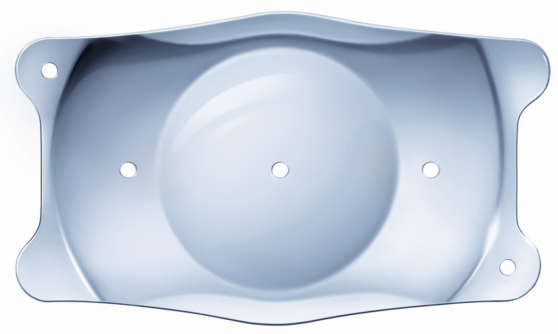

Die implantierbare „Kontaktlinse“

Die EVO ICL ist eine klare Linse aus Kunststoff, die einer Kontaktlinse ähnelt. Da sie klein und extrem weich ist, kann sie problemlos gefaltet werden und mit einem Injektor innerhalb von Sekunden – durch einen kleinen Zugang in der Hornhaut – sanft im Auge platziert werden.

Die implantierbare „Kontaktlinse“

Die EVO ICL ist eine klare Linse aus Kunststoff, die einer Kontaktlinse ähnelt. Da sie klein und extrem weich ist, kann sie problemlos gefaltet werden und mit einem Injektor innerhalb von Sekunden – durch einen kleinen Zugang in der Hornhaut – sanft im Auge platziert werden.